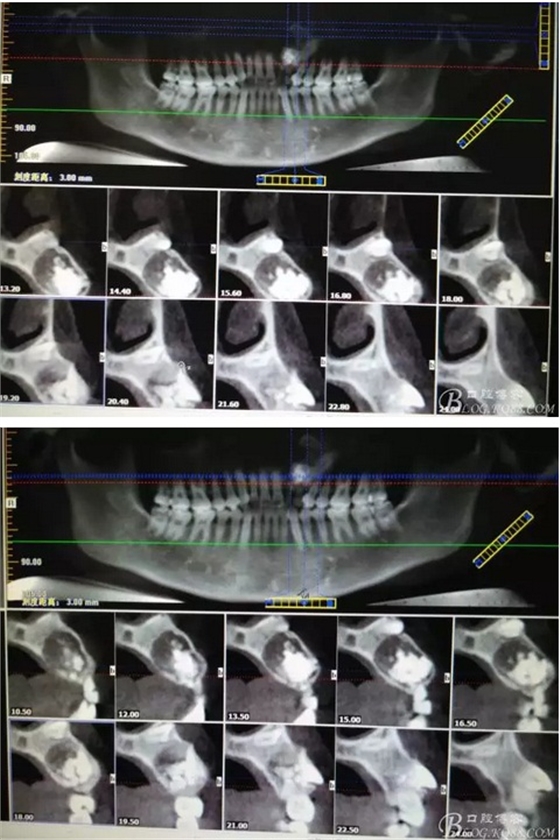

圖1。術前的CBCT影像檢查:22位于鼻底下方,23位于24、25的根方。左側(cè)乳Ⅱ、Ⅲ根方顯示囊性改變,囊腔內(nèi)大量致密鈣化團塊,密度高。